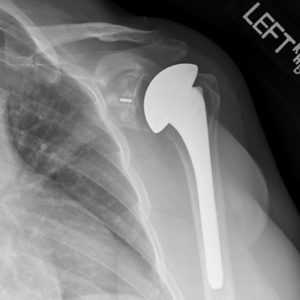

Рентген после эндопротезирования плечевого сустава

Если ранее человеку стоило больших трудов и страданий, к примеру, завести руку за голову или спину, отвести ее в сторону, поднять вверх или удержать даже самый легковесный предмет, то после установки эндопротеза обо всех этих трудностях реально забыть. Однако произвести исключительно замену сочленения недостаточно, пациенту необходимо после нее упорно работать над своим восстановлением, чтобы однозначно получить отличный положительный эффект от пройденного хирургического мероприятия.

- Аппаратные методы в отдаленные сроки предназначены для наблюдения за правильностью положения, глубиной посадки, целостностью протезной конструкции. Они основаны на применении способов рентгенографии.